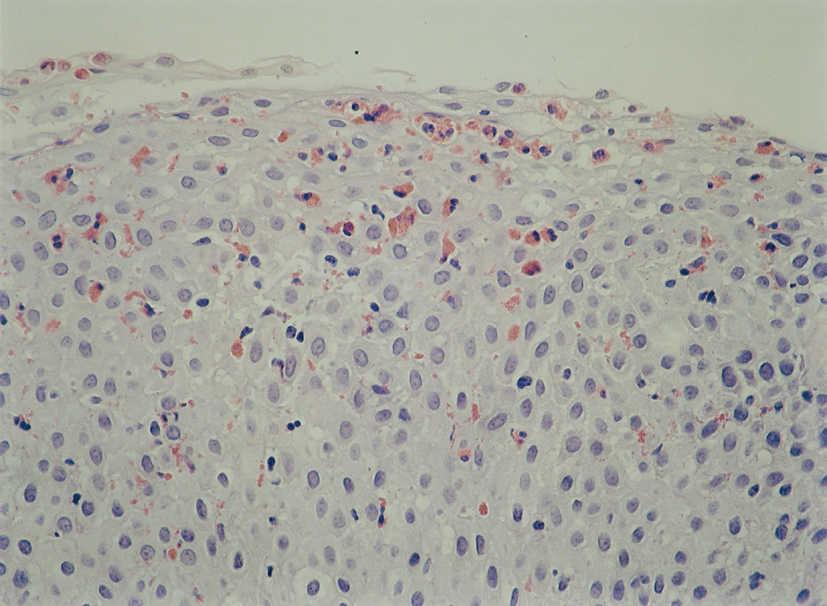

Figura 3. Microabscesos eosinofílicos que protruyen sobre la luz esofágica que se corresponden con las imágenes objetivadas en la figura 2. (Hematoxilina-eosina, x40.)

La anatomía patológica mostraba en todos los pacientes presencia de eosinófilos en mucosa esofágica en número superior a 20 por campo de gran aumento, de predominio peripapilar, así como hiperplasia epitelial (fig. 4). En 5 casos (45,45 %) se encontró un recuento aumentado de eosinófilos en antro gástrico y segunda porción de duodeno, por lo cual se realizó con posterioridad fibrocolonoscopia. En todos ellos se observaba una eosinofilia mucosa por encima de los valores normales en íleon terminal, colon y recto-sigma, que fue diagnosticada de gastroenteropatía eosinofílica con afectación generalizada (fig. 5).

En cuanto a los hallazgos endoscópicos pueden ir desde un aspecto de la mucosa esofágica estrictamente normal a diferentes patrones de alteración endoscópica. Se ha descrito la existencia de imágenes erosivas longitudinales, granularidad, pérdida del patrón vascular, estenosis focales6, estenosis de larga extensión ("esófago de pequeño calibre")17 y fragilidad mucosa de fácil erosión al contacto con el endoscopio (denominado como crêpe paper esophagus)18. Pero el patrón que se ha comunicado con más frecuencia es el de traquealización esofágica, denominado de este modo por la presencia de imágenes de anillos transversales consecutivos que recuerdan el aspecto "corrugado" de la tráquea y que corresponderían a contracciones intermitentes de la musculatura circular esofágica19. Otra imagen bastante característica en estos pacientes es un punteado blanquecino que semeja el aspecto de candidiasis esofágica y que corresponde a acumulaciones o microabscesos constituidos por eosinófilos que protruyen sobre la superficie mucosa, como se demuestra por el estudio anatomopatológico20,21. En dos de nuestros pacientes se demostró este hallazgo.

Como hemos citado anteriormente, el hallazgo anatomopatológico característico de esta entidad es la importante infiltración eosinófila (> 20 eosinófilos por campo de gran aumento) que puede presentarse en cualquiera de sus capas, si bien predomina en la mucosa, en el epitelio peripapilar y en la lámina propia, de los tercios superior y medio esofágicos. Otros hallazgos característicos son los agregados o microabscesos de eosinófilos superficiales antes comentados, las papilas elongadas y la hiperplasia epitelial basal. Estudios ecoendoscópicos realizados en estos pacientes ponen de manifiesto el aumento en el espesor tanto de la mucosa, de la submucosa y de la muscularis mucosae, sin apreciarse cambios significativos en las capas de la musculatura circular22.